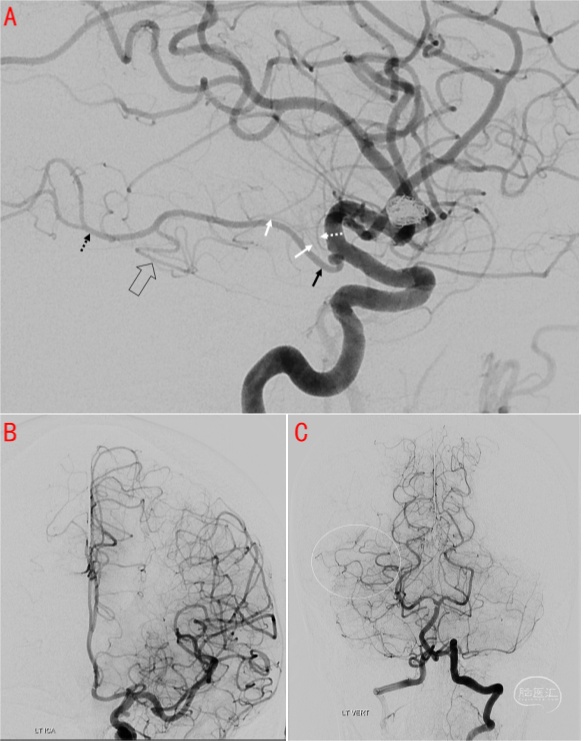

2.3 脉络膜前动脉供血的丘脑动静脉畸形

图15 左侧丘脑动静脉畸形伴出血患者。术前核磁T2像(A)显示左侧脉络膜前动脉增粗,左侧颈内动脉斜位造影(B)显示动静脉畸形由左侧脉络膜前动脉及脉络膜后外侧动脉供血,脉络点如图中所示。C显示术中微导管在微导丝支撑下越过脉络点并接近畸形团。D为术中XperCT证实微导管头端位于出血动静脉畸形团后外侧。